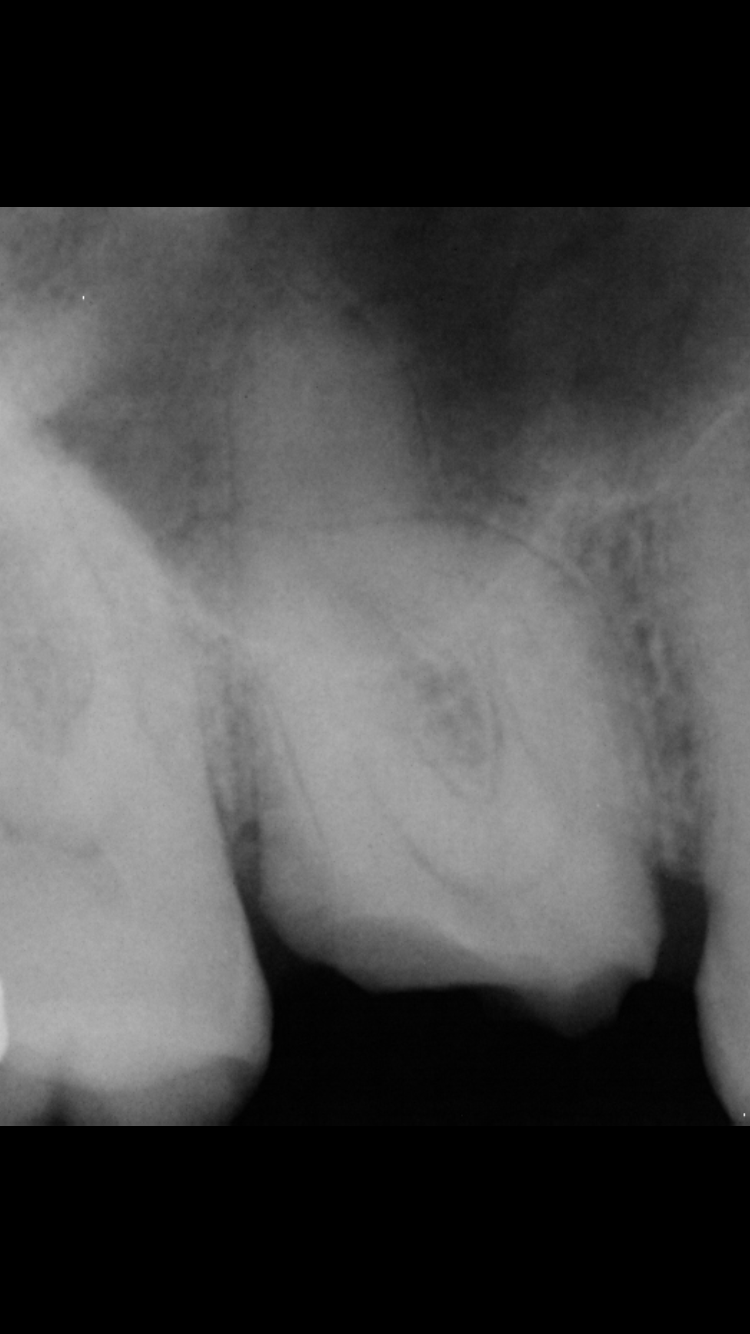

This is a right maxillary first molar (tooth #3) that required root canal therapy because decay developed under an old existing crown. This root canal was complicated because of a severe curvature (dilaceration) in multiple canals. Extra care, time, and the use of additional instruments was required to treat this tooth adequately to avoid future symptoms and infection.